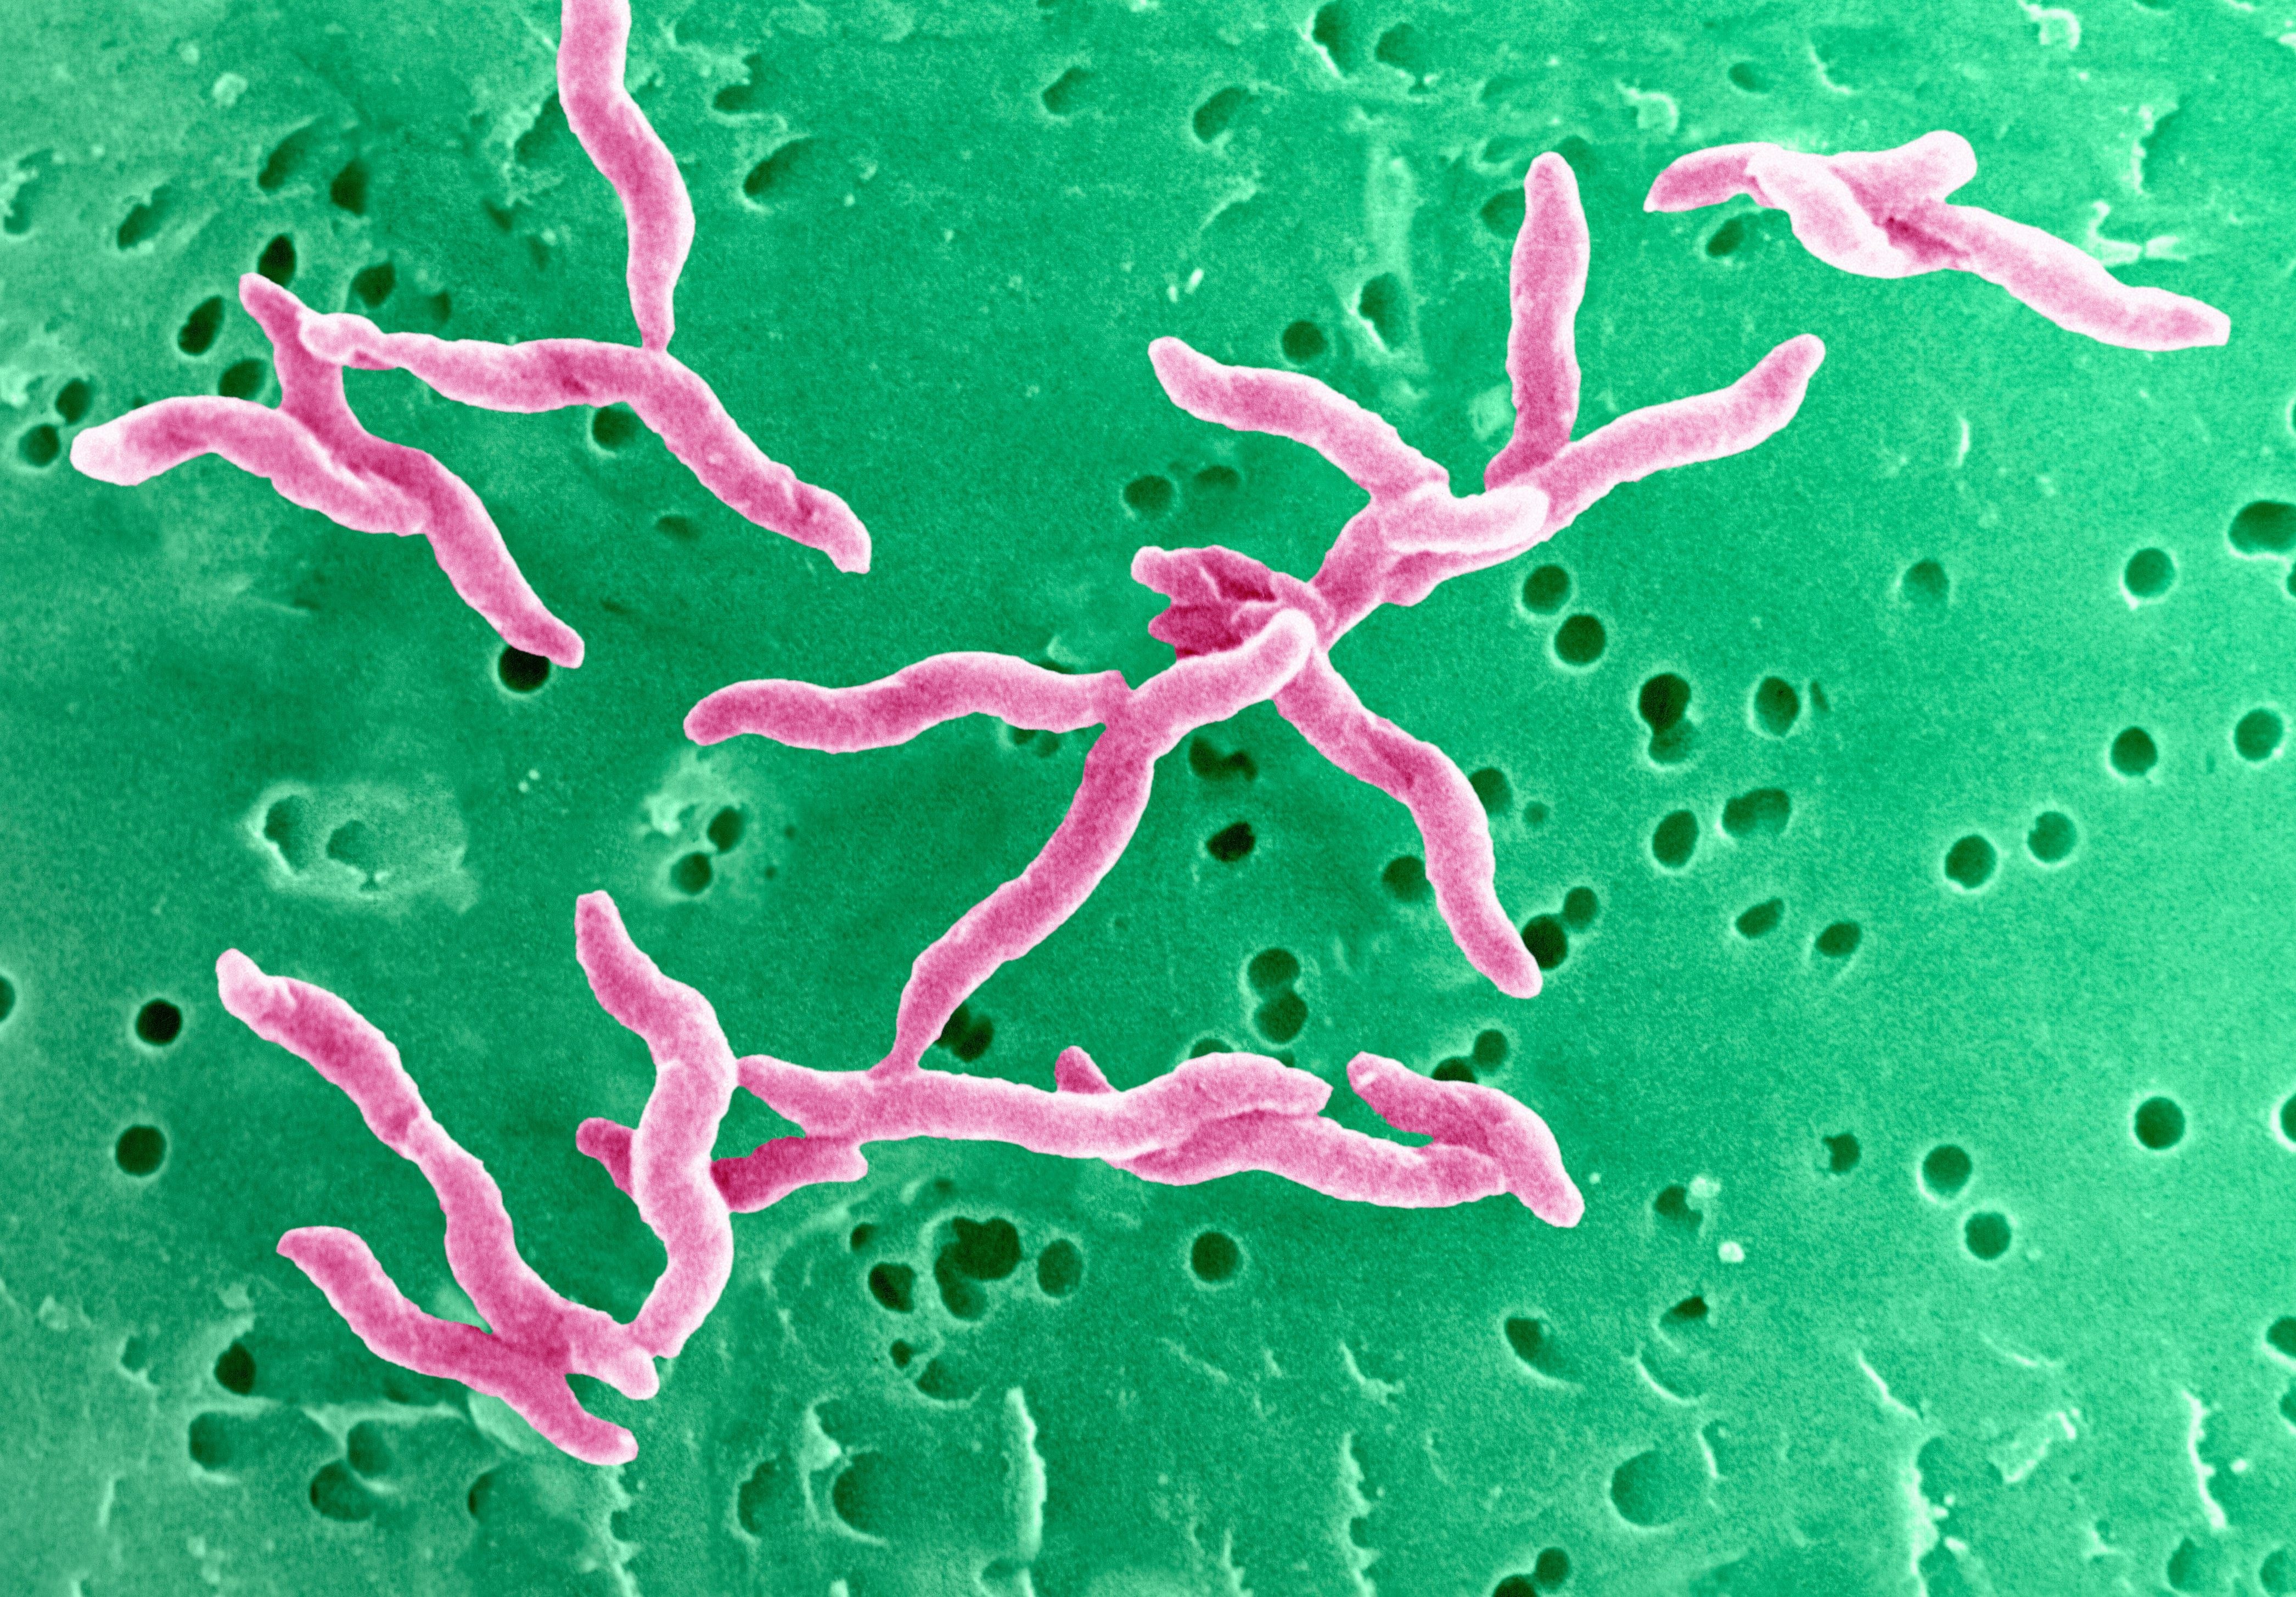

Кампилобактер фетус: патогенез и инфекции

Раздел: Другие животные